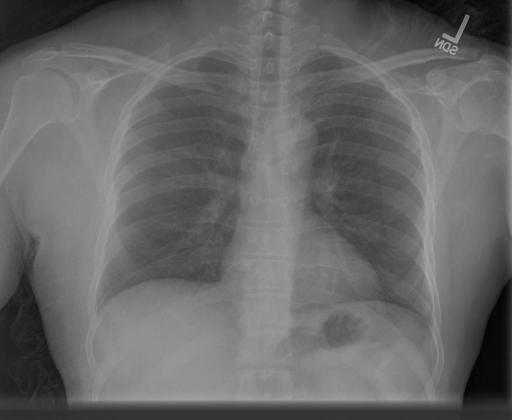

We display qualitative results in Fig. 3. The annotators tend to be content with most annotations. There are edits at the extensions of the esophagus, trachea, and aorta and corrections of the lower ribs. There is little consensus for classes in the abdominal area, such as the stomach, as seen on the right of Fig. 3 . In contrast, the annotators often align for bone classes.

We show the quantitative segmentation performance against medical expert annotations for all classes in Fig. 3 . The dashed lines represent the IAA, whereas the dotted line displays the average MAA. As the task for the human annotators was not to annotate from scratch but to correct wrong pixel-wise predictions, we can see a high MAA for most classes. In the frontal view, the most significant disagreements exist for rare bone structures such as L3 and C4, lower ribs, the mediastinal distribution, or the breast tissue. The IAA and MAA are highly similar with mIoU of respective 95% and 94%. The Hausdorff distance for MAA is slightly lower than the IAA, indicating slight differences in boundary annotations while maintaining a considerable overlap with the other annotator. In the lateral view, the concrete delineation of rib structures appears ambiguous, leading to lower MAA and IAA with a greater IAA than MAA for all metrics in this supercategory. Overall there is less agreement between the medical experts in the lateral view, leading to a better average MAA than IAA across all metrics (i.e. 85% vs 83% mIoU). While the experts propose changes to the original predictions, they are often not overlapping. In the lateral view, rib segmentations can become quite hard to interpret. While both annotators disagree with the rib segmentations, they do not always agree on how they should look. Similarly to the frontal view, tube-like structures like the esophagus are extended as they can appear fractured at times.